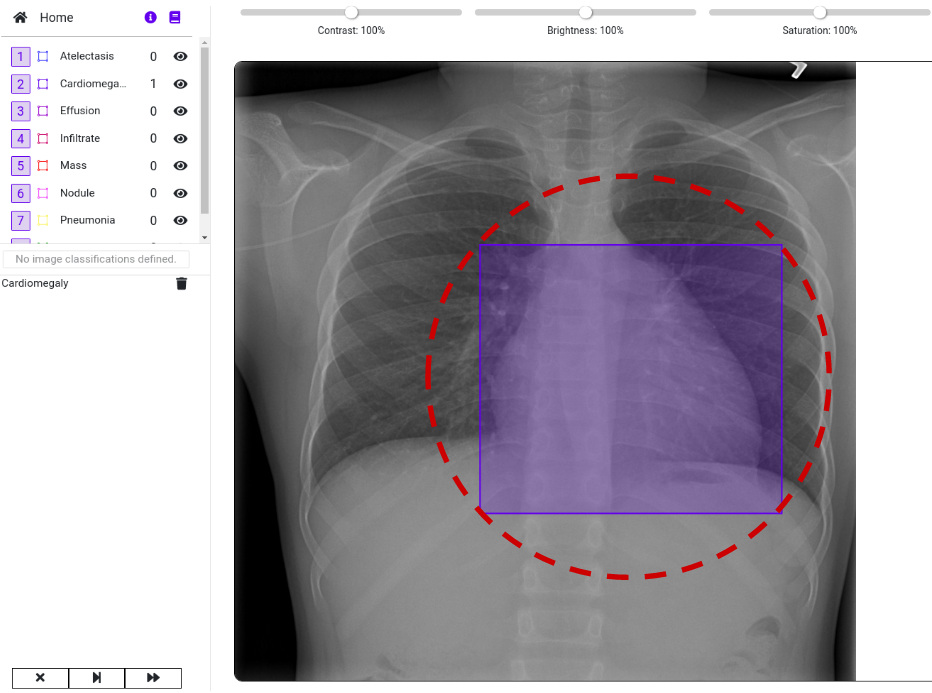

- A set of 880 X-ray images. In this example image we already marked the predicted location of the disease with a red circle:

Our goal is to import the images and the labeled data into a DataGym Project. This allows the labelers to view the predicted diseases and to correct the size and location of the labels if necessary. Instead of labeling images from scratch, labelers have now the reduced task of correcting pre-labeled images. As you can see in the image below, we imported both the image and its respective label. Thereby, we directly depict the bounding box from the .csv file to identify the affected region in the X-ray image.

Visit DataGym to inspect your labeled images. As you can see in the image below, we imported both the image and its respective label. Thereby, we directly depict the bounding box from the .csv file to identify the affected region in the X-ray image. Feel free to browse through the images within your Project to see more examples. There are also multiple ways to design your own Label configuration for your own Projects. We recommend using this real-life example to further explore the functionalities of DataGym and its Python API.